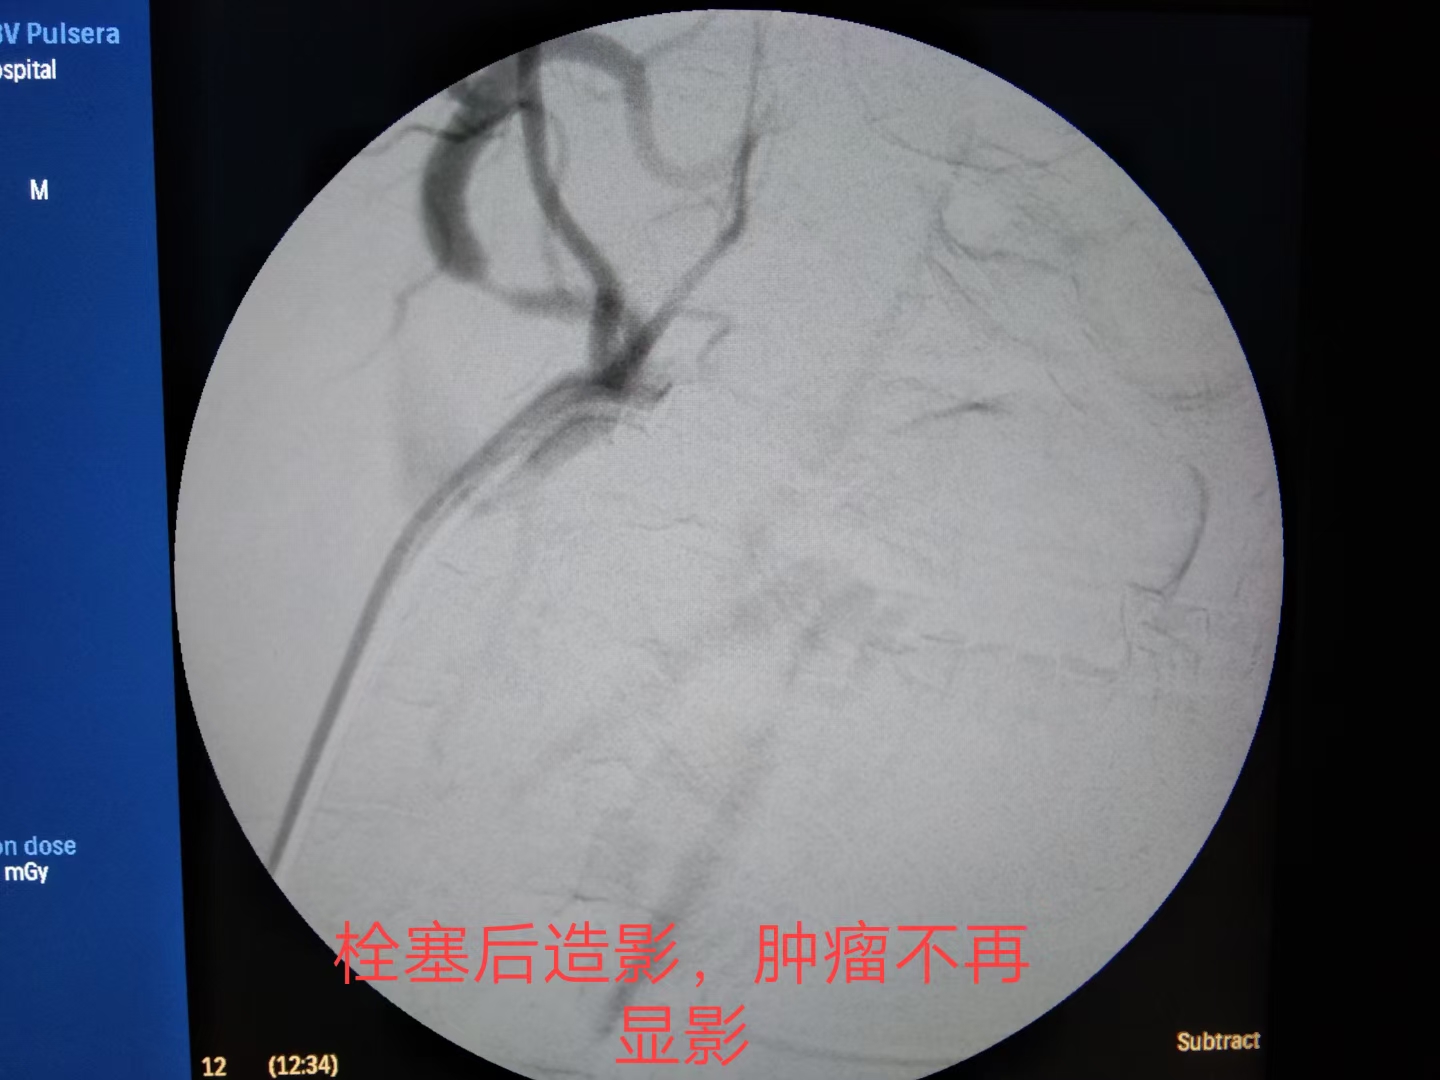

最终,颗粒+弹簧圈完美栓塞。出血停止,患者生命体征平稳。

此时可通过 介入的方法进行止血治疗 ,在介入设备的引导下,插入导管、导丝,对出血的部位进行造影,并堵住血管,进行止血,可达到治疗的目的,最大限度的减少损伤, 同时患者 在较短时间内可恢复到出血前的状态 。